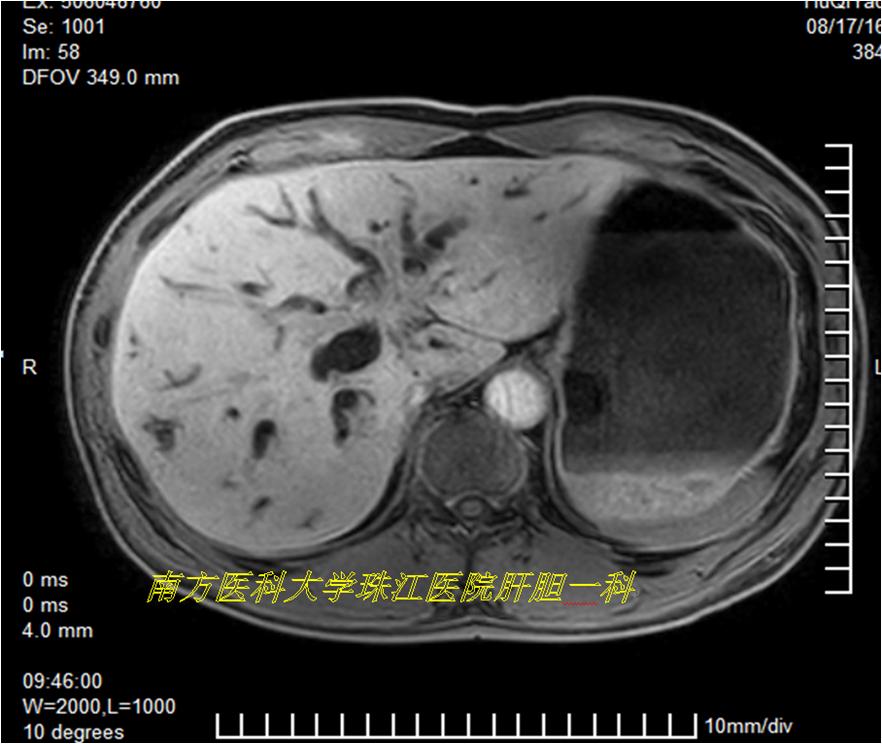

慕名前往,完成老李的三维可视化模型,发现肝动脉及门静脉均存在变异,如果术前未发现这两处变异,贸然进行手术很可能出现相关的并发症。

在三维可视化指导下,方驰华教授团队“顺藤摸瓜”成功地为老李进行肝门部胆管癌根治性切除术,术中情况跟术前三维重建模型完全一致。术后顺利康复出院。